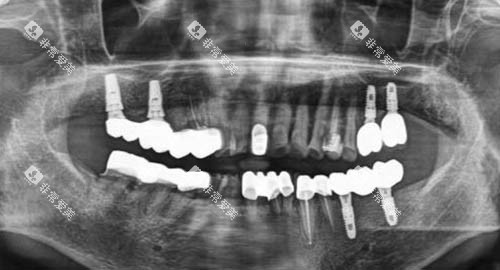

从普通的牙齿清洁、补牙,到复杂的牙齿矫正、种植牙手术,这里都配备了相应的特色设备和经验充足的医生团队。

例如,他们拥有靠前的口腔全景CT机,能够清晰地拍摄口腔内部的三维图像,为医生比较准诊断病情提供有力依据。